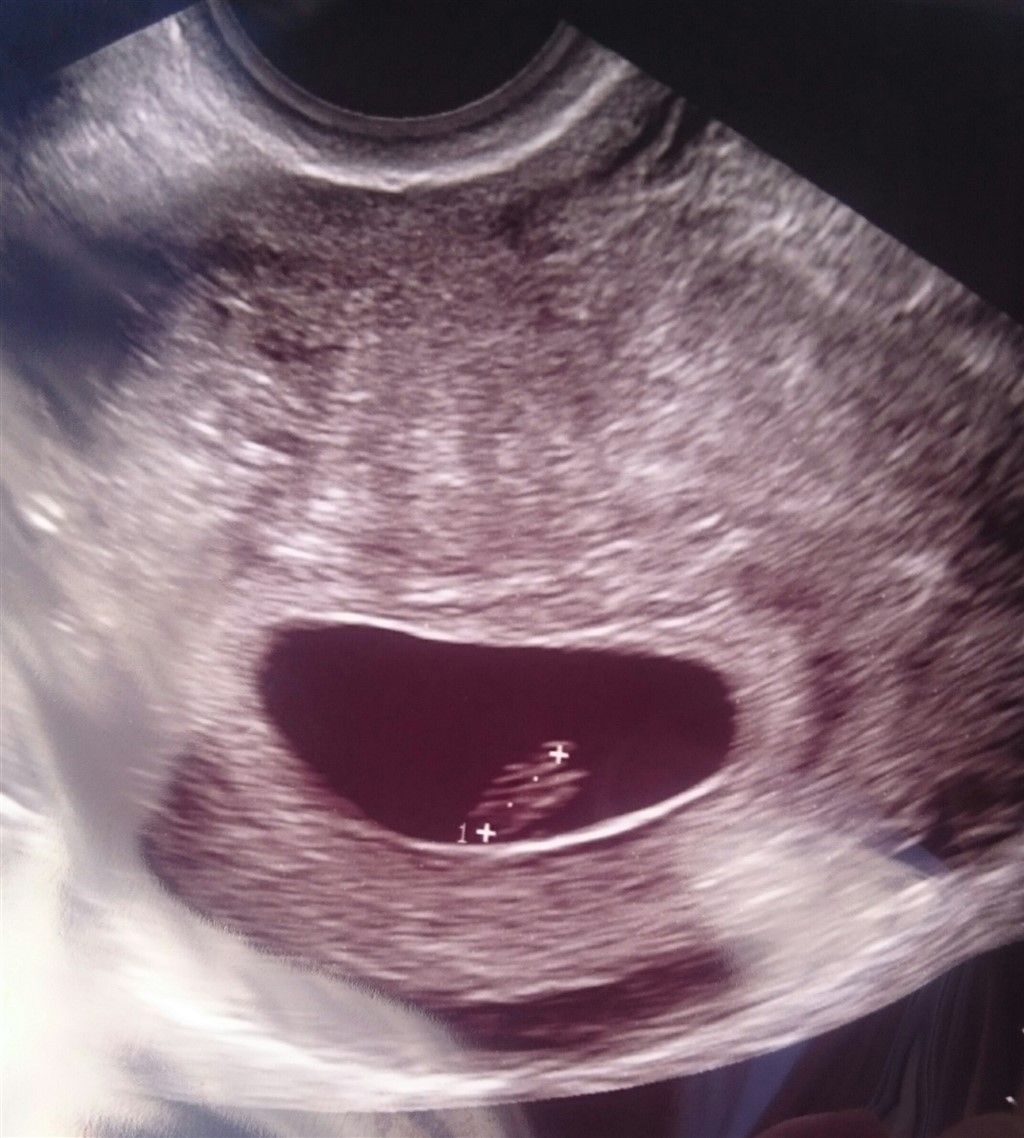

I dag, 2 uger efter, har jeg været til scanning og her så jeg en lille blyp med hjerteblink

Er 6+3 indtil videre, da nakkefoldscanningen jo vil være mere præcis.